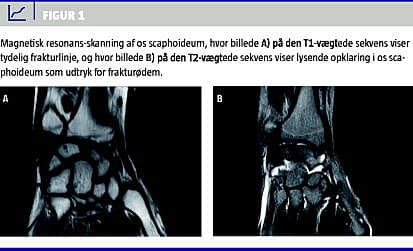

Ud over scaphoideum-frakturerne påviste radiologerne såvel som reservelægerne ni distale radiusfrakturer samt to epifysiolyser, som ikke blev diagnosticeret ved den primære røntgenundersøgelse, hvilket svarer til en sensitivitet og specificitet på 100% (Figur 1 ).